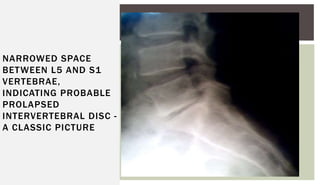

X-Ray : lumbo-sacral spine;

Narrowed disc spaces.

NARROWED SPACE

BETWEEN L5 AND S1

VERTEBRAE,

INDICATING PROBABLE

PROLAPSED

INTERVERTEBRAL DISC -

A CLASSIC PICTURE